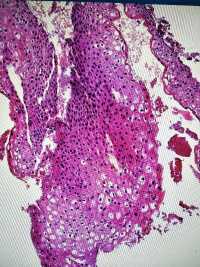

CIN1?

图1

图2

图3

图4

LSIL。

其实lsil的诊断一致性很低,上海的标准诊断lsil比较严格,似是而非者为非,本例属于似是而非,按我们的日常则争议比较多,我觉得综合看吧,阴道镜表现,hpv和tct检测结果来综合判断。

谢谢各位老师,TCT报ASCUS,患者自述HPV59阳